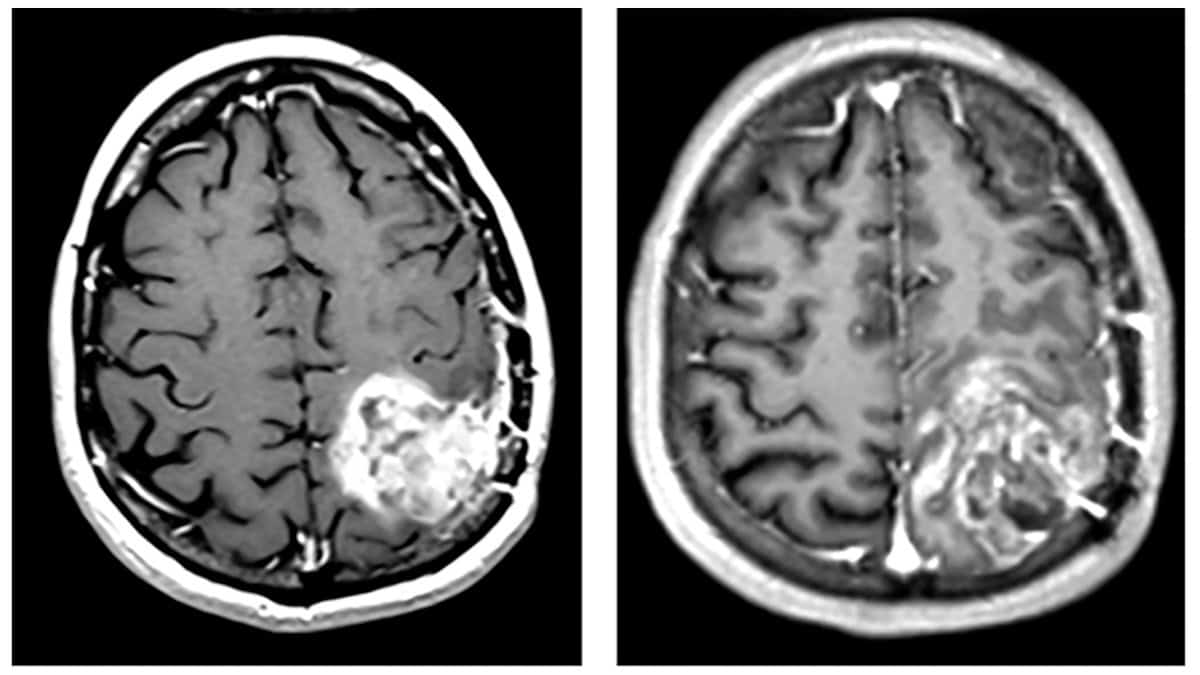

Brain MR images before and after TheraBionic treatment

Clinical response MR images from a patient with glioblastoma obtained before (left) and after (right) treatment with the TheraBionic device emitting GBMF. Post-treatment scans exhibited a more heterogeneous and ill-defined enhancement pattern than the initial scans, suggestive of treatment effect rather than tumour progression. (Courtesy: CC BY 4.0/Oncotarget 10.18632/oncotarget.28770)

Finally, the researchers used the TheraBionic device to treat two patients: a 38-year-old patient with recurrent glioblastoma and a 47-year-old patient with the rare brain tumour oligodendroglioma. The first patient showed signs of clinical and radiological benefit following treatment; the second exhibited stable disease and tolerated the treatment well.